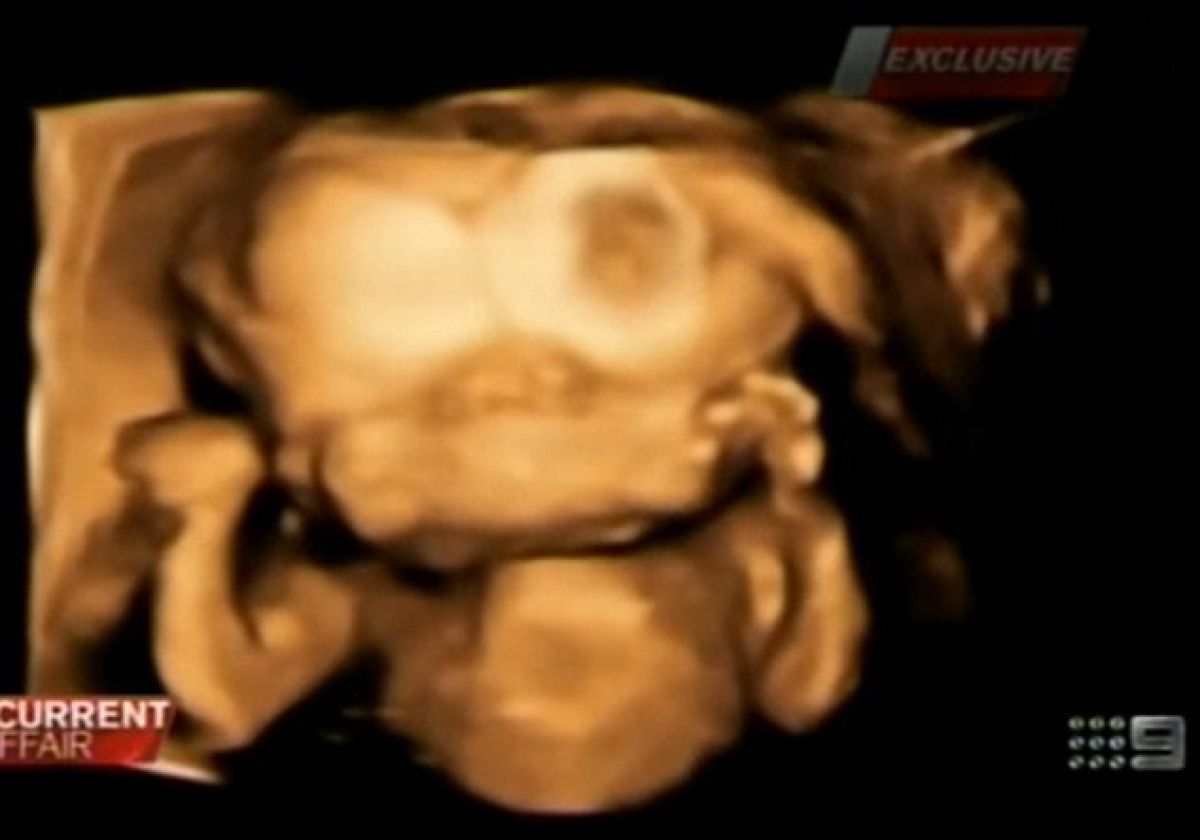

Renee Young in Simon Howie, ki prihajata iz Sydneyja sta na rutinskem pregledu ob 15. tednu nosečnosti izvedela grozljivo novico. Čisto običajni pregled z ultrazvokom je pokazal, da mama v trebuhu nosi otroka z enim telesom in eno glavo, ki ima dva obraza in dvoje možgan, povezanih z možganskim deblom. Do sedaj je bilo na svetu le 35 podobnih primerov. Zdravniki so Renee in Simonu svetovali naj Renee naredi splav, saj okolica takšnega otroka ne bo nikoli sprejela in bodo nanj gledali kot na pošast.